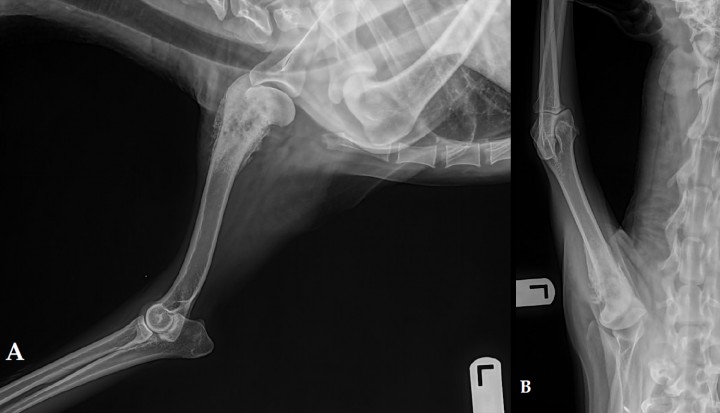

En la mayoría de los casos, previamente a la cirugía, el apoyo de peso sobre la extremidad afectada ya está disminuido por lo que el paciente se acostumbra rápidamente en el postoperatorio a caminar sobre los tres miembros restantes. El tiempo medio máximo de adaptación es de 4 semanas y el índice de satisfacción de los propietarios tras la cirugía es muy alto.[ Kirpensteijn J, van den Bos R, Endenburg N. Adaptation of dogs to the amputation of a limb and their owners’ satisfaction with the procedure. Vet Rec. 1999;144(5):115-8. [PubMed] ] La mayoría de los pacientes son ambulatorios a las 24 horas tras la cirugía (Fig. 7 A y B).[ Liptak JM, Dernell WS, Farese JP, Worley DR. Musculosdeletal system. En:Veterinary Surgical Oncology. Kuding ST, Séguin B. Ed Willey Blackwell. West Essex, UK. 2012.491-560. , Kirpensteijn J, van den Bos R, Endenburg N. Adaptation of dogs to the amputation of a limb and their owners’ satisfaction with the procedure. Vet Rec. 1999;144(5):115-8. [PubMed] ] La velocidad de adaptación no se ve afectada por el peso, la edad o la amputación del miembro torácico o pélvico.[ Kirpensteijn J, van den Bos R, Endenburg N. Adaptation of dogs to the amputation of a limb and their owners’ satisfaction with the procedure. Vet Rec. 1999;144(5):115-8. [PubMed] ] Se debe realizar fisioterapia postoperatoria en perros con sobrepeso y en aquellos con alguna enfermedad ortopédica tal como osteoartritis (aunque en casos significativamente afectados preoperatoriamente, la amputación estaría contraindicada).

<p>La amputación de las extremidades es una cirugía bien tolerada, incluso en razas grandes. Un paciente 5 días tras la cirugía (A) y 1 día tras la cirugía (B).</p>

Figura 7

La amputación de las extremidades es una cirugía bien tolerada, incluso en razas grandes. Un paciente 5 días tras la cirugía (A) y 1 día tras la cirugía (B).